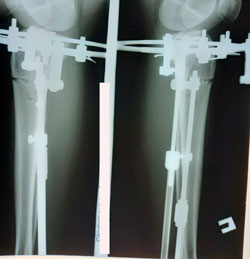

Исходник - 36 лет.

Дата операции - 02.12.2020

Ещё раз: невозможно устранить варусную деформацию при помощи круропластики

Очередной пример!

перед фиксацией